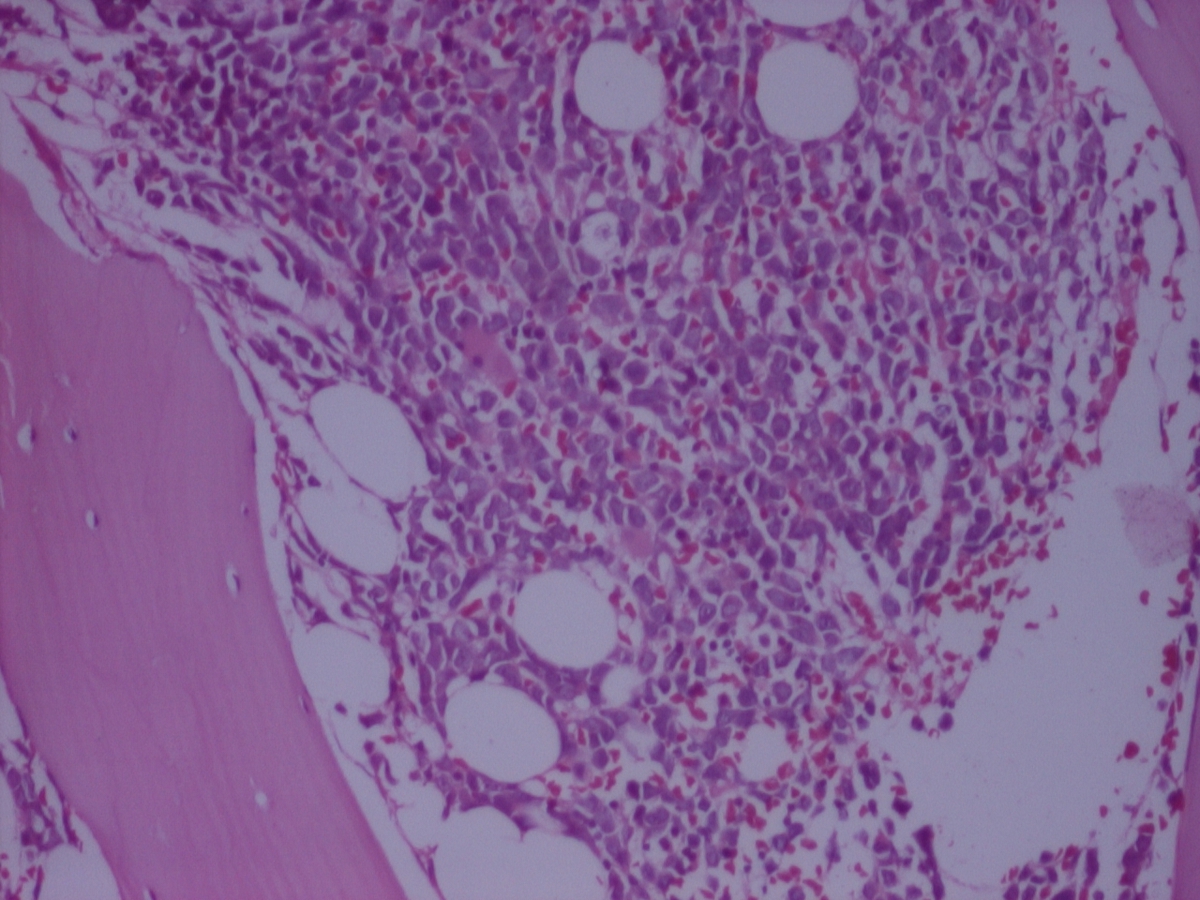

Bone Marrow biopsy shows 70-80% of cellularity and diffuse infiltration by large blasts that are more than 20% with evident and pink cytoplasm. There is marked decrease of the trilineage hematopoiesis. Reticulin fibers are increase.

| BM biopsy | ![]() |